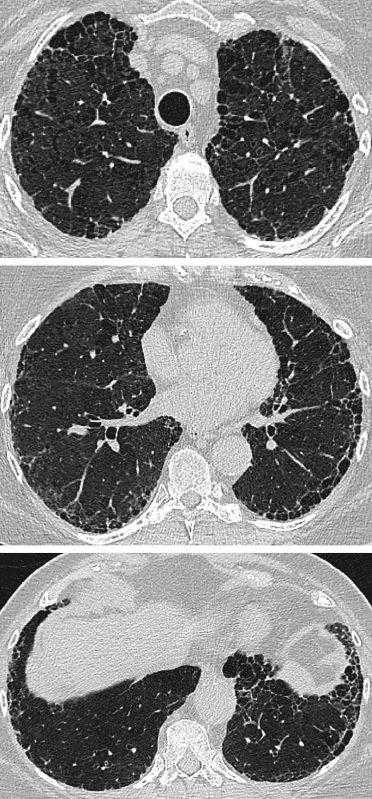

图3:HRCT显示典型的肺纤维化和肺气肿(间隔旁肺气肿模式)的典型分布。67岁男性,诊断为特发性肺纤维化,广泛孤立的间隔旁和小叶中央肺气肿出现在上部区域。尽管小叶中央型肺气肿多孤立于中段,但间隔旁肺气肿越来越混杂,类似于左肺中的蜂窝状囊肿。在左下叶内,间隔旁的肺气肿类似蜂窝囊肿,与形状不规则的小叶中心型肺气肿相邻。

图4:HRCT显示混合性破坏性肺气肿恶化(合并肺纤维化和肺气肿,混合型)。一位66岁男性特发性肺纤维化患者的(A和B)肺上区和(C和D)肺下区,相隔2年(A和C:基线;B和D:随访)的轴位图像中,随着时间的推移,右上叶的孤立性肺气肿与纤维化混合在一起。在左下叶,中央位置的肺气肿变得分离(牵引性肺气肿),并随着周围纤维化的进展而扩大。

图5:HRCT显示肺气肿合并肺活检证实的脱屑性间质性肺炎(合并肺纤维化和肺气肿,HRCT混合模式)。低衰减区混杂有磨玻璃样阴影(高衰减)和小叶间隔增厚。

图6:HRCT显示混合性肺气肿和纤维化伴厚壁大囊肿(肺纤维化和肺气肿合并,厚壁大囊肿模式)。组织病理学显示主要与吸烟相关的间质纤维化。